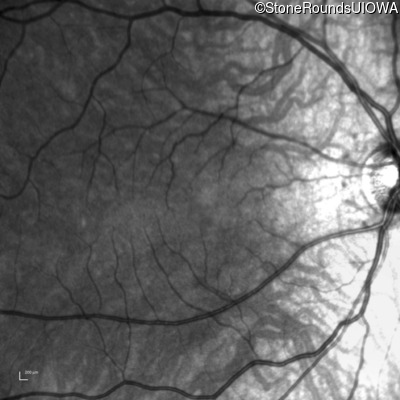

Infrared Fundus Photograph - Right - 20/125

Exemplar